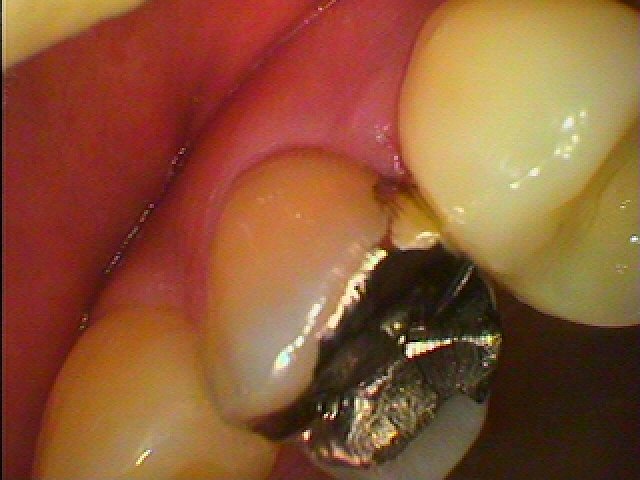

このような銀歯が入っています

かなり大きな銀歯人あります